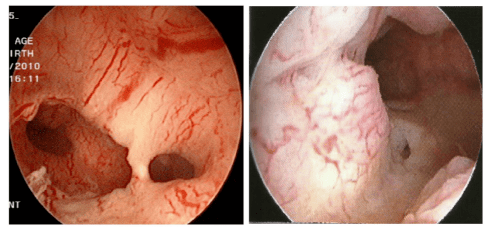

宫腔镜下见子宫内膜癌病灶 (见粗大异性血管)

宫腔镜下可见子宫内膜癌组织上血供丰富,组织糟脆.